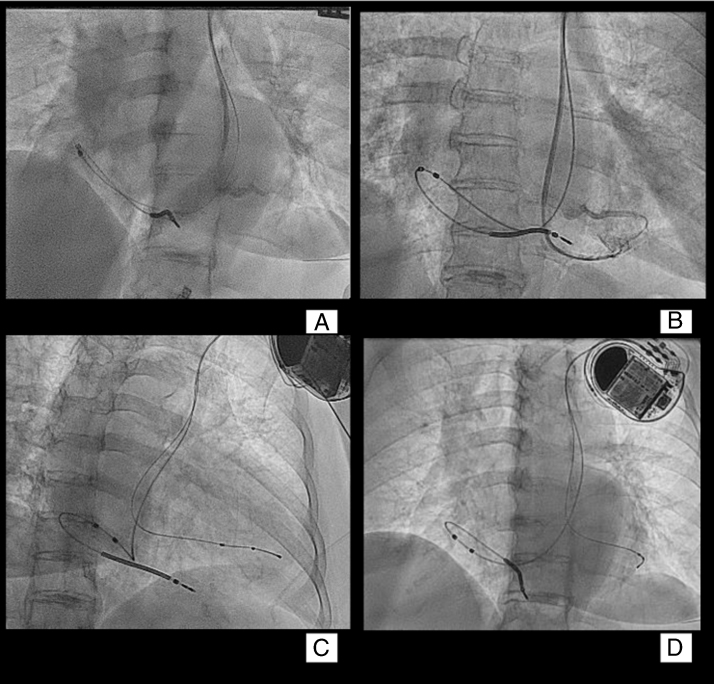

Figure 2.

A: Venogram taken from the persistent left superior vena cava showing a posterior coronary vein suitable for left ventricle (LV) lead placement. Note the high-lateral right atrial placement of the atrial sensing dipole. B: Selective venogram from the posterior vein. C: Right anterior oblique view of the active fixation lead placed in the posterior coronary vein chosen as target. D: Left anterior oblique view of the active fixation LV lead placed inside the target coronary vein.